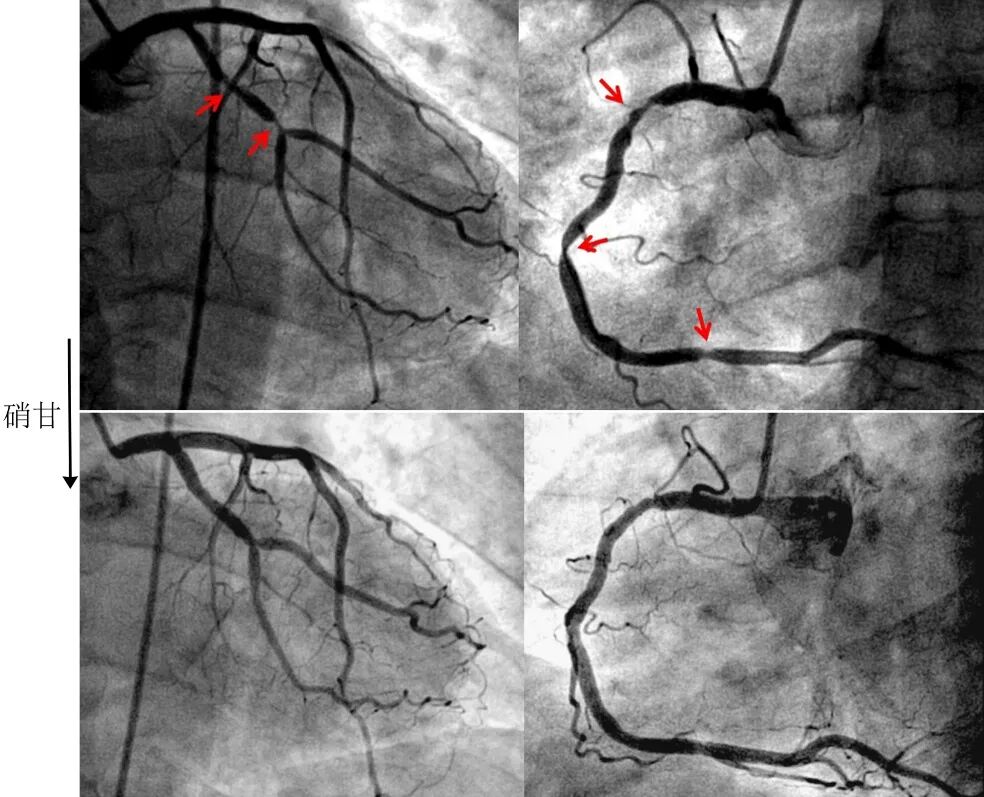

多支血管弥漫性狭窄一旦具有以下反常表现,需要警惕痉挛的可能(图4):(1)多支狭窄具有“细小”、“光滑和对称”的特点;(2)缺乏除烟酒外经典的危险因素,与严重冠脉病变不符;(3)平时活动耐量可,与严重冠脉病变不符;(4)心脏大小和功能可,与严重冠脉病变不符。

图4冠脉痉挛表现为多支狭窄[2]

51岁吸烟男性,凌晨急性胸痛30分钟,心电图II、III、avF、V5-6导联ST段抬高,急诊造影显示回旋支2处狭窄,右冠3处狭窄,冠脉内注射硝酸甘油后均缓解,心电图ST段回落,症状缓解。